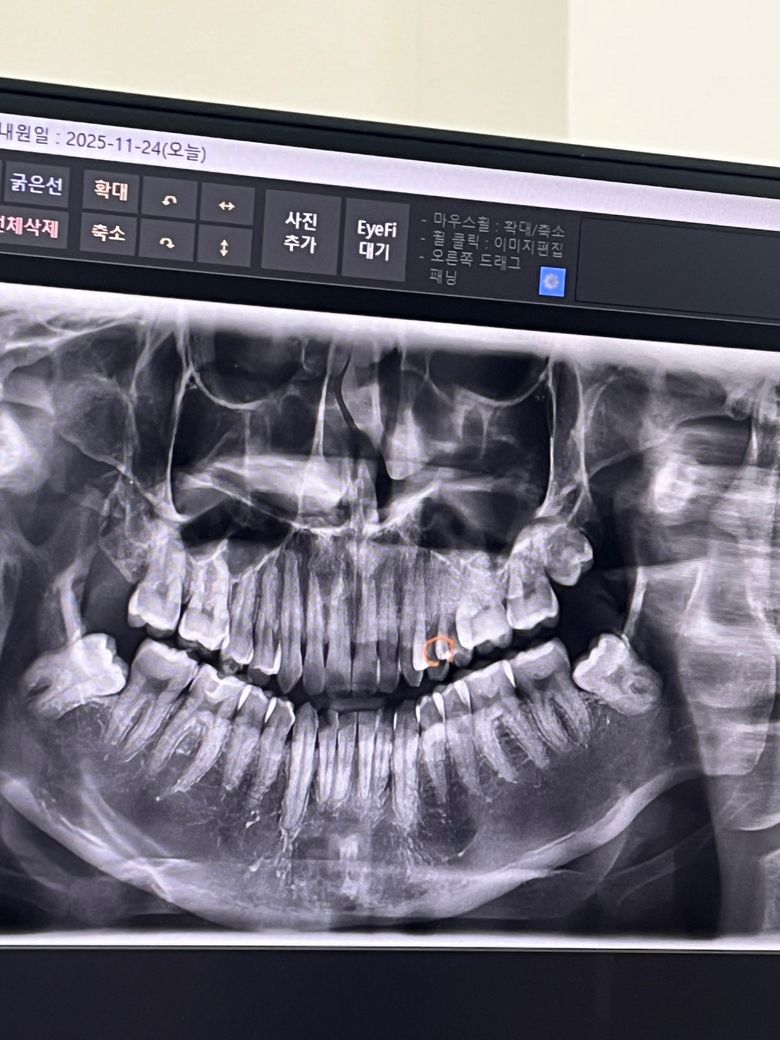

충치가 많은가요? 엑스레이 사진 첨부합니다.

사진 상 치료해야할 충치가 많은가요..ㅜㅜ

일단 동그라미 친 부분은 신경치료도 받고 인레이도 했습니다…

16번과 46번도 인레이 했었는데…

사진 상으로 조언 부탁드려요

엑스레이 상으로는 인접면 충치가 있는거 같습니다. 신경치료를 해야될 치아라고 표시한부분은 작은 엑스레이 사진이 필요해 보입니다.

파노라마 사진상으로는 충치에 대한 정확한 진단 하지 않습니다. 치아끼리 다 중첩되어서 의미있는 정보를 얻을 수도 없고요. 일단 17,27,37,45 추가적으로 작은 엑스레이 찍어보면 좋을 것 같습니다